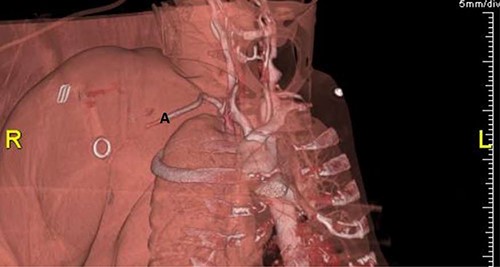

Plain radiographs of the right humerus and shoulder did not show any fracture or dislocation. A computed tomography (CT) scan with arterial phase angiography did not show and acute fracture of the cervical spine, but did reveal an abrupt cessation in flow in the right axillary artery secondary to traumatic occlusion of the vessel at the junction of segment 2 going into segment 3 with significant surrounding haematoma (Figs. 1 and 2).

CT angiography reconstructed views demonstrating absent flow beyond segment 1 of the right axillary artery (A) with haematoma in the right axilla (H).